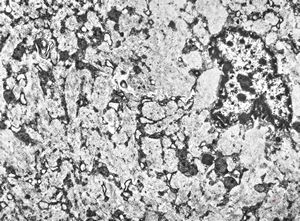

bone marrow … plasmocytoma (parafin-embedded sample)